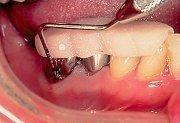

1

| 術直前にアタッチメントレベルを計測しておく(この時点で歯肉は可及的に健康な状態にしておく)。 |